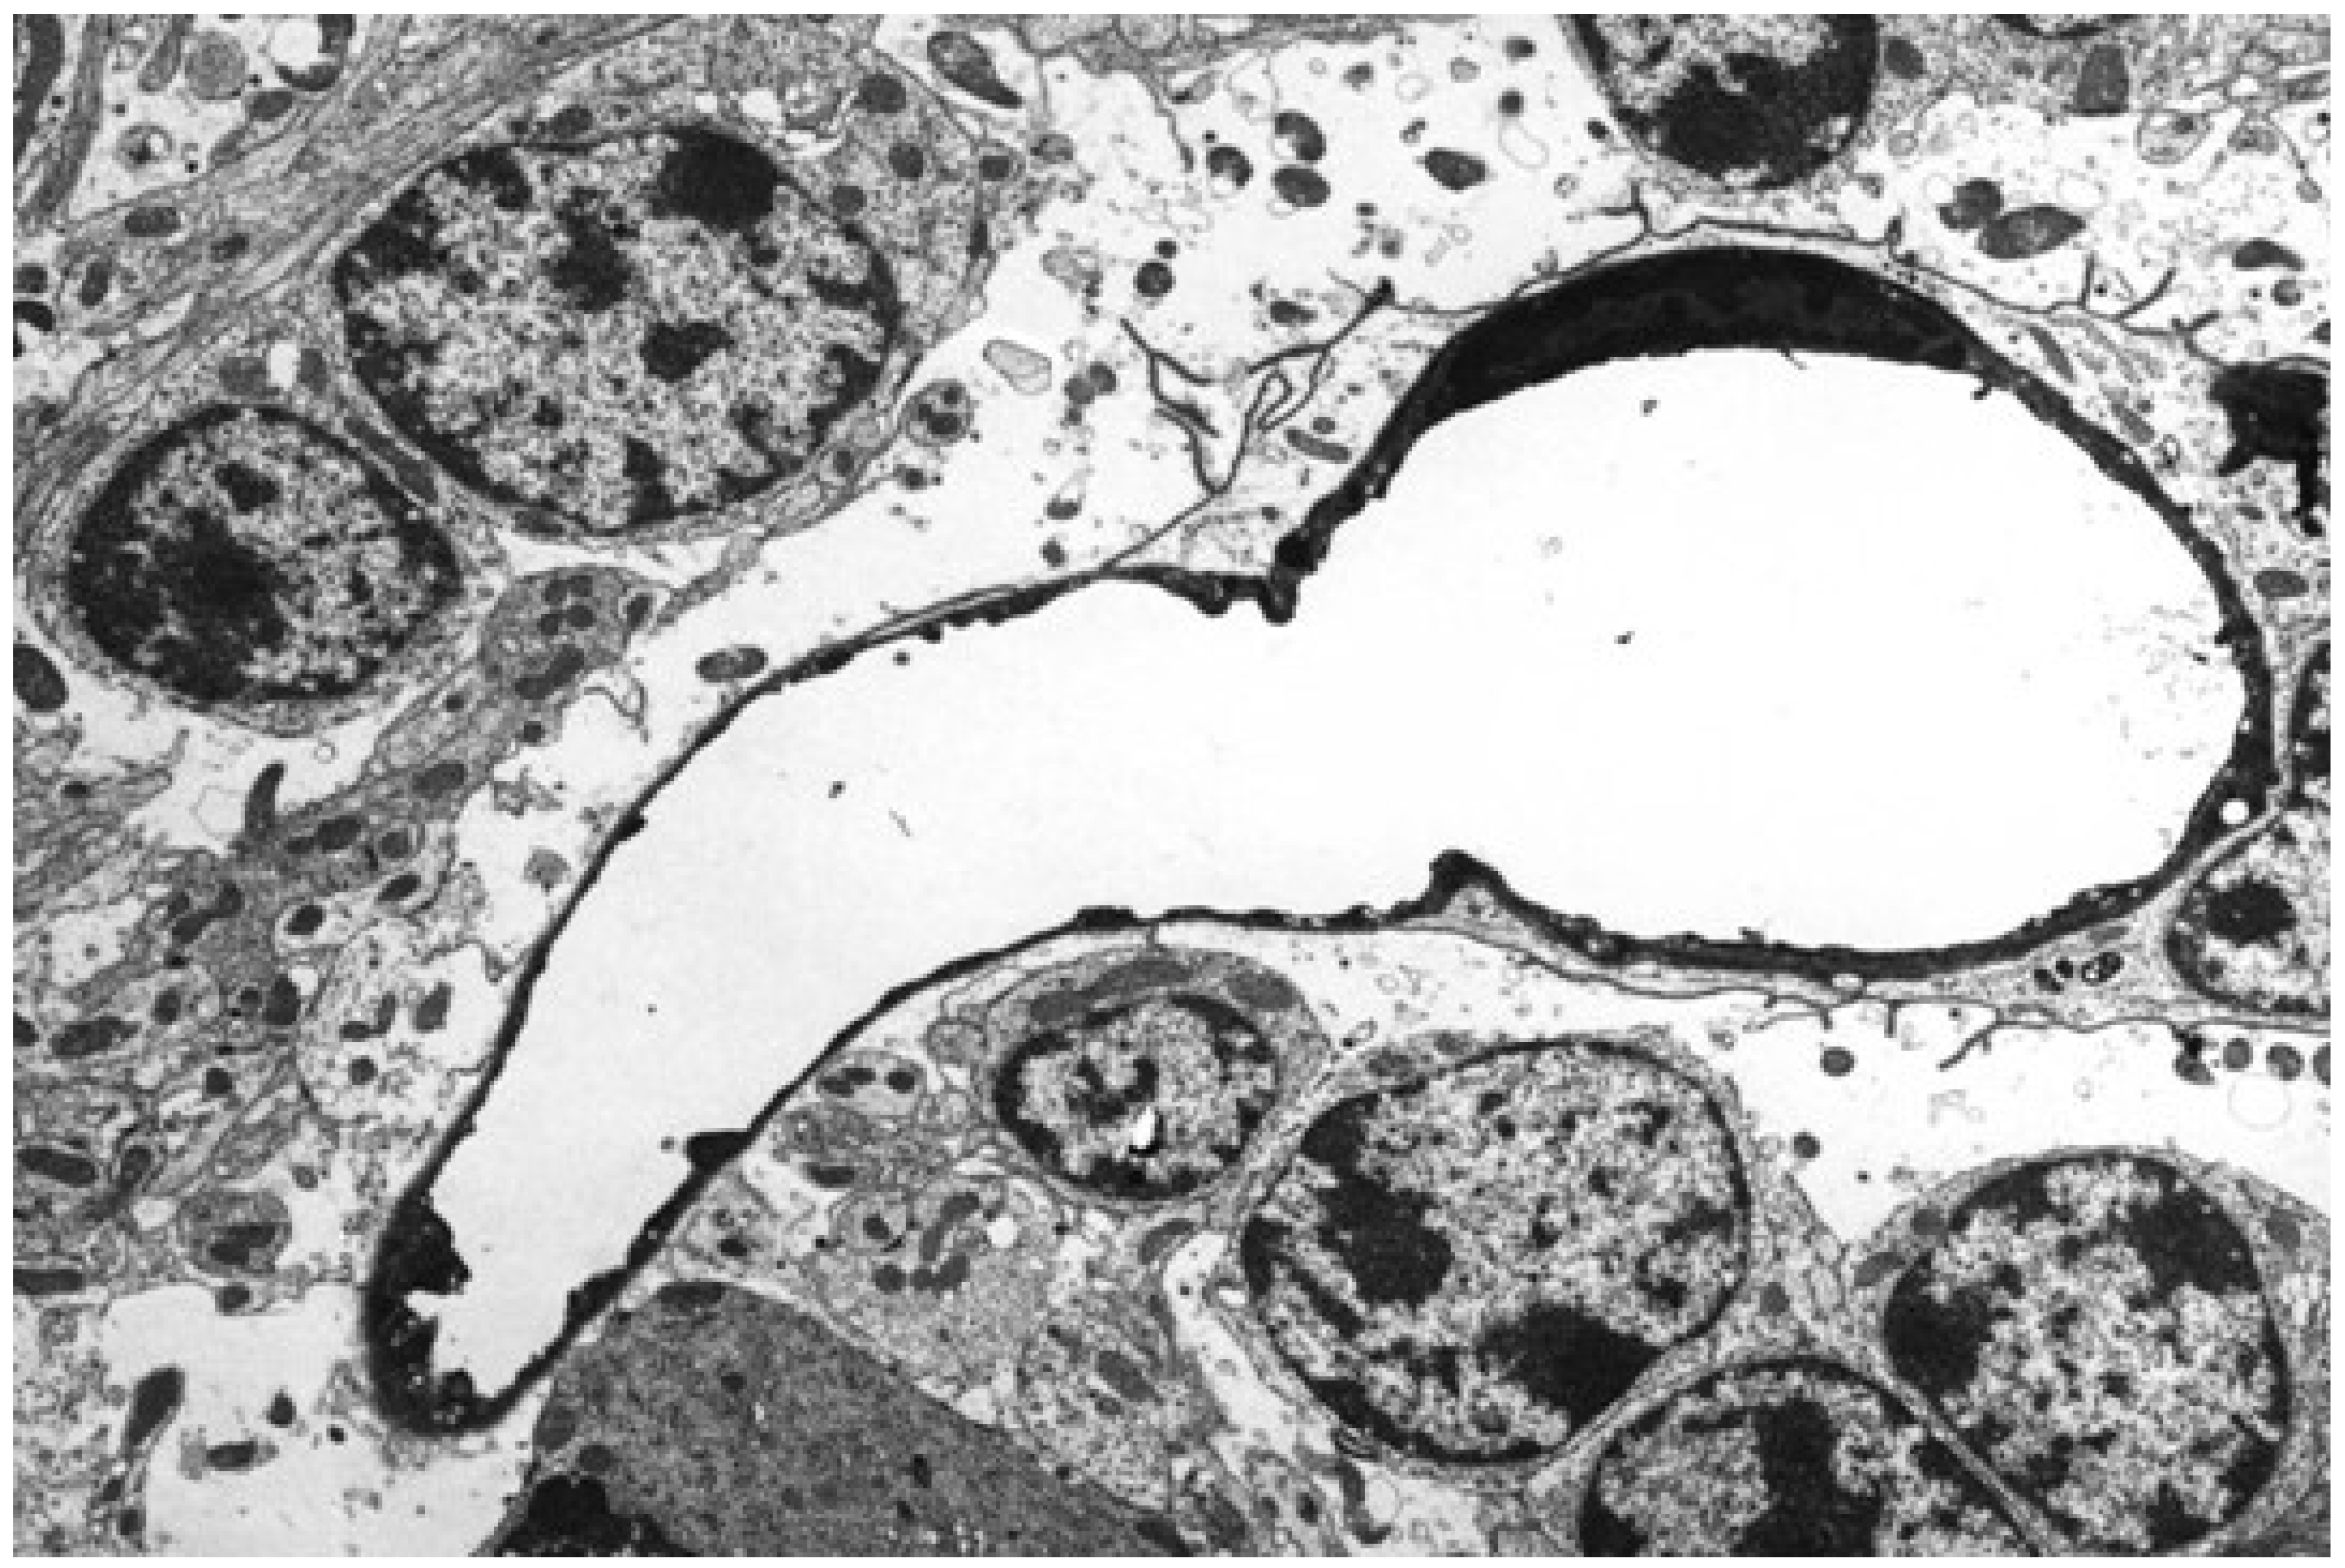

- Morgan, K.T.; Kelly, B.G. Ultrastructural study of brain lesions produced in mice by the administration of Clostridium welchii type D toxin. J. Comp. Pathol. 1974, 84, 181–191. [Google Scholar] [CrossRef]

- Finnie, J.W. Ultrastructural changes in the brain of mice given Clostridium perfringens type D epsilon toxin. J. Comp. Pathol. 1984, 94, 445–452. [Google Scholar] [CrossRef]